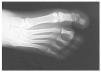

Aconsejamos reposo con la extremidad elevada durante 3 días, permitiendo apoyo de talón en la deambulación. Posteriormente inició carga parcial con bastones. Los puntos de sutura fueron retirados a los 10 días y realizamos control radiológico a los 15 días (fig. 5, 6). A las tres semanas se autorizó la carga y se iniciaron ejercicios activos de la articulación5.

Fig. 6.—Se confirma la reducción en la proyección DP. Fig. 6.—Reduction in dorso-plantar projection is confirmed.